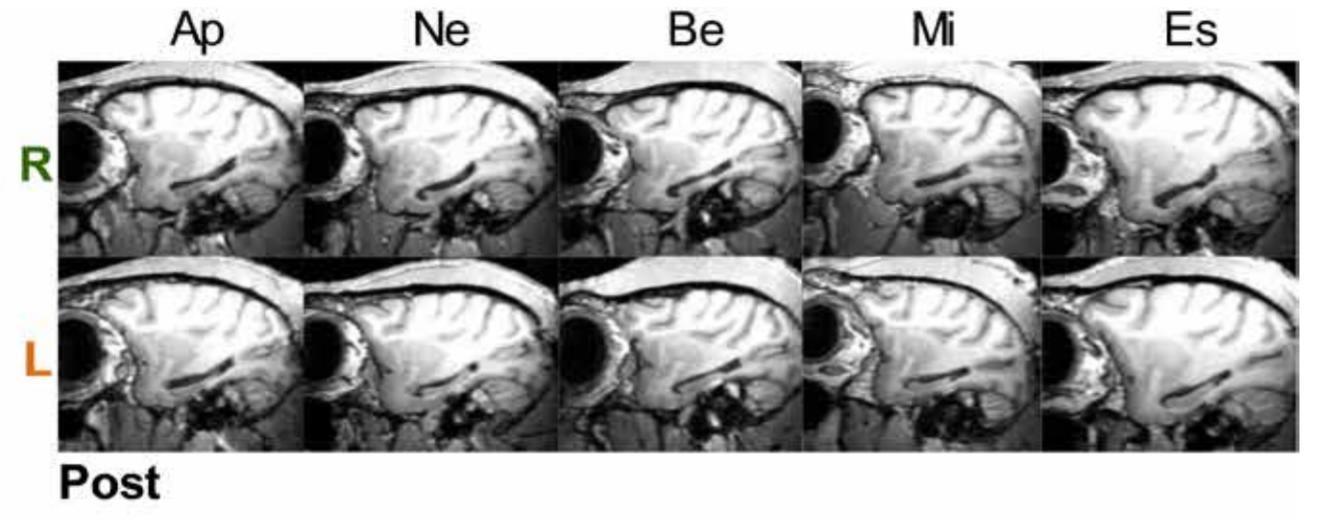

Нейробиологи провели ряд когнитивных тестов с макаками-резусами с поврежденным гиппокампом: несмотря на общепринятые представления, нарушения гиппокампа не повлияли на память и другие когнитивные способности животных. Авторы статьи, опубликованной в журнале Science Advances, считают, что необходимо переоценить роль других структур мозга в когнитивных функциях, которые принято связывать с гиппокампом.